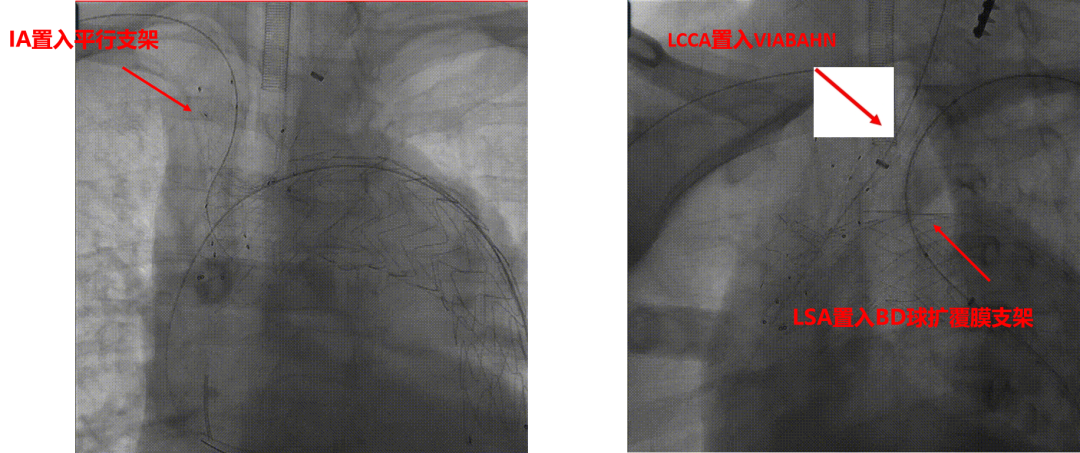

★ Case6:男,55岁, 胸痛4天入院。诊断:A型主动脉夹层

3D打印模型

分支前后体外预开窗

术毕造影

术后CTA